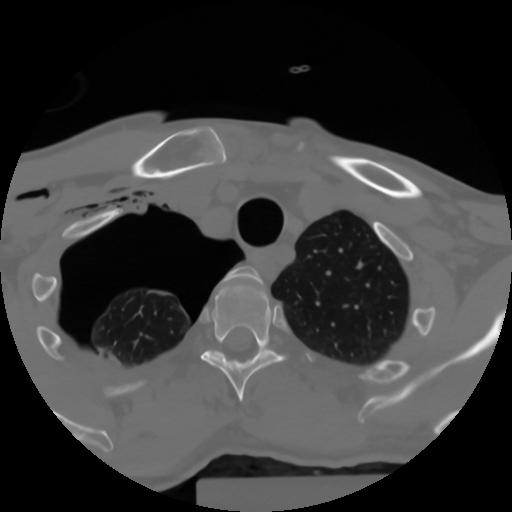

10 P.BLANDAS,,Axial,2.0,P.BLANDAS,,